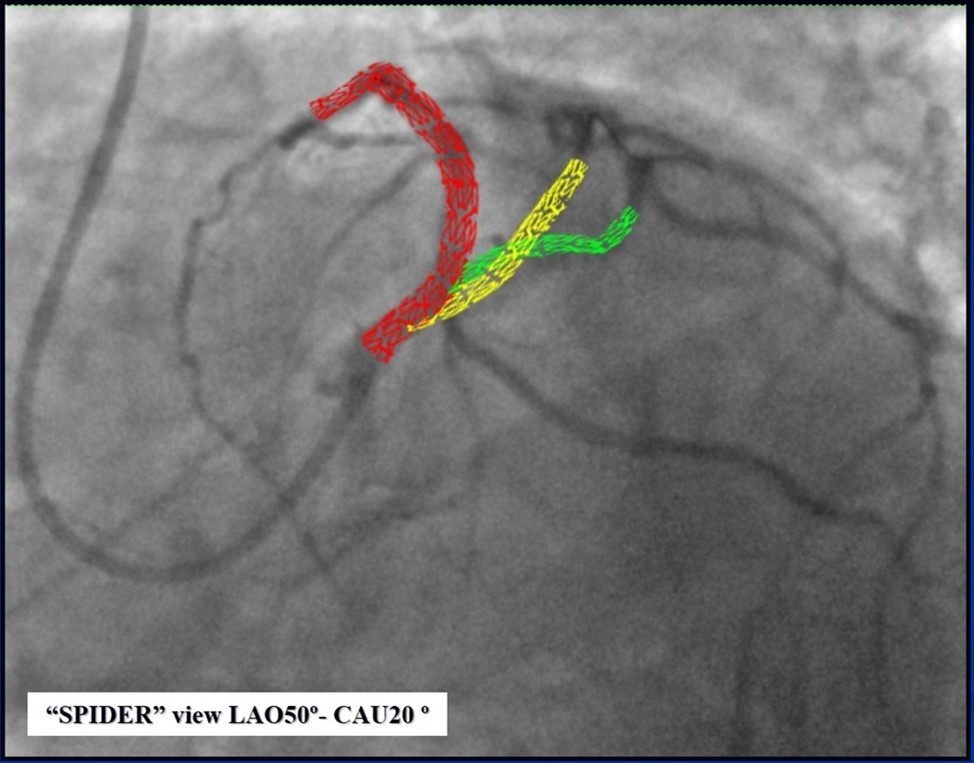

Due to financial problems the second stage was performed after 3 months (during this time the patient solved his financial problems). CAG revealed patent stents in LAD (Figure 7), and 60-70% restenosis by BMS in RCA (Figure 8). In-stent restenosis was treated by plain old balloon angioplasty (POBA), the optimal result was obtained (Figure 9). After LMCA quadrifurcation balloon predilation, 2.5×26 mm DES (Resolute Integrity, Medtronic) was implanted in the IMA, using a modified balloon mini-crush technique. The stent was minimally protruded in the LMCA and its edge was crushed by preloaded MB balloon. Next 2.5×30 mm DES (Resolute Integrity, Medtronic) was implanted in OM1 through the CX (first marginal and circumflex arteries in this particular case have the same ostium). The stent was protruded in the LMCA as in conventional modified balloon crush stenting technique, after stent deployment, its balloon was pulled back and overinflated, then protruded stent was crushed by preloaded MB balloon (Figure 10). 3.5×15 mm DES was implanted in the LMCA so that distal part of the stent covered ostial and proximal segments of the LAD. Sequential post-dilatations were performed using a kissing balloon technique (1. LMCA-LAD-IMA,2. LMCA-LAD-CX-1OM). After post-dilatations, through the stent implanted in CX-OM1, coronary wire and smaller diameter balloon (2.0 mm) were advanced in direction of the CX mid-segment and by balloon dilatation stent’s strut was opened (provisional stenting technique for CX). Finally, the proximal optimization technique was performed in the LMCA using a 3.5 mm diameter non-compliant balloon (Figure 11). The final angiographic image was good, the intervention ended without complications (Figure 11, Figure 12). We could not confirm the result with IVUS or OCT due to several technical and financial problems (not covered by insurance). 1 month after PCI, at regular checkout, the ejection fraction was 48%, the functional class of the Congestive Heart Failure decreased from class II-III to class I and the patient complaints have been disappeared.

Figure 12.Schematic presentation of the implanted stents, “spider” projection.